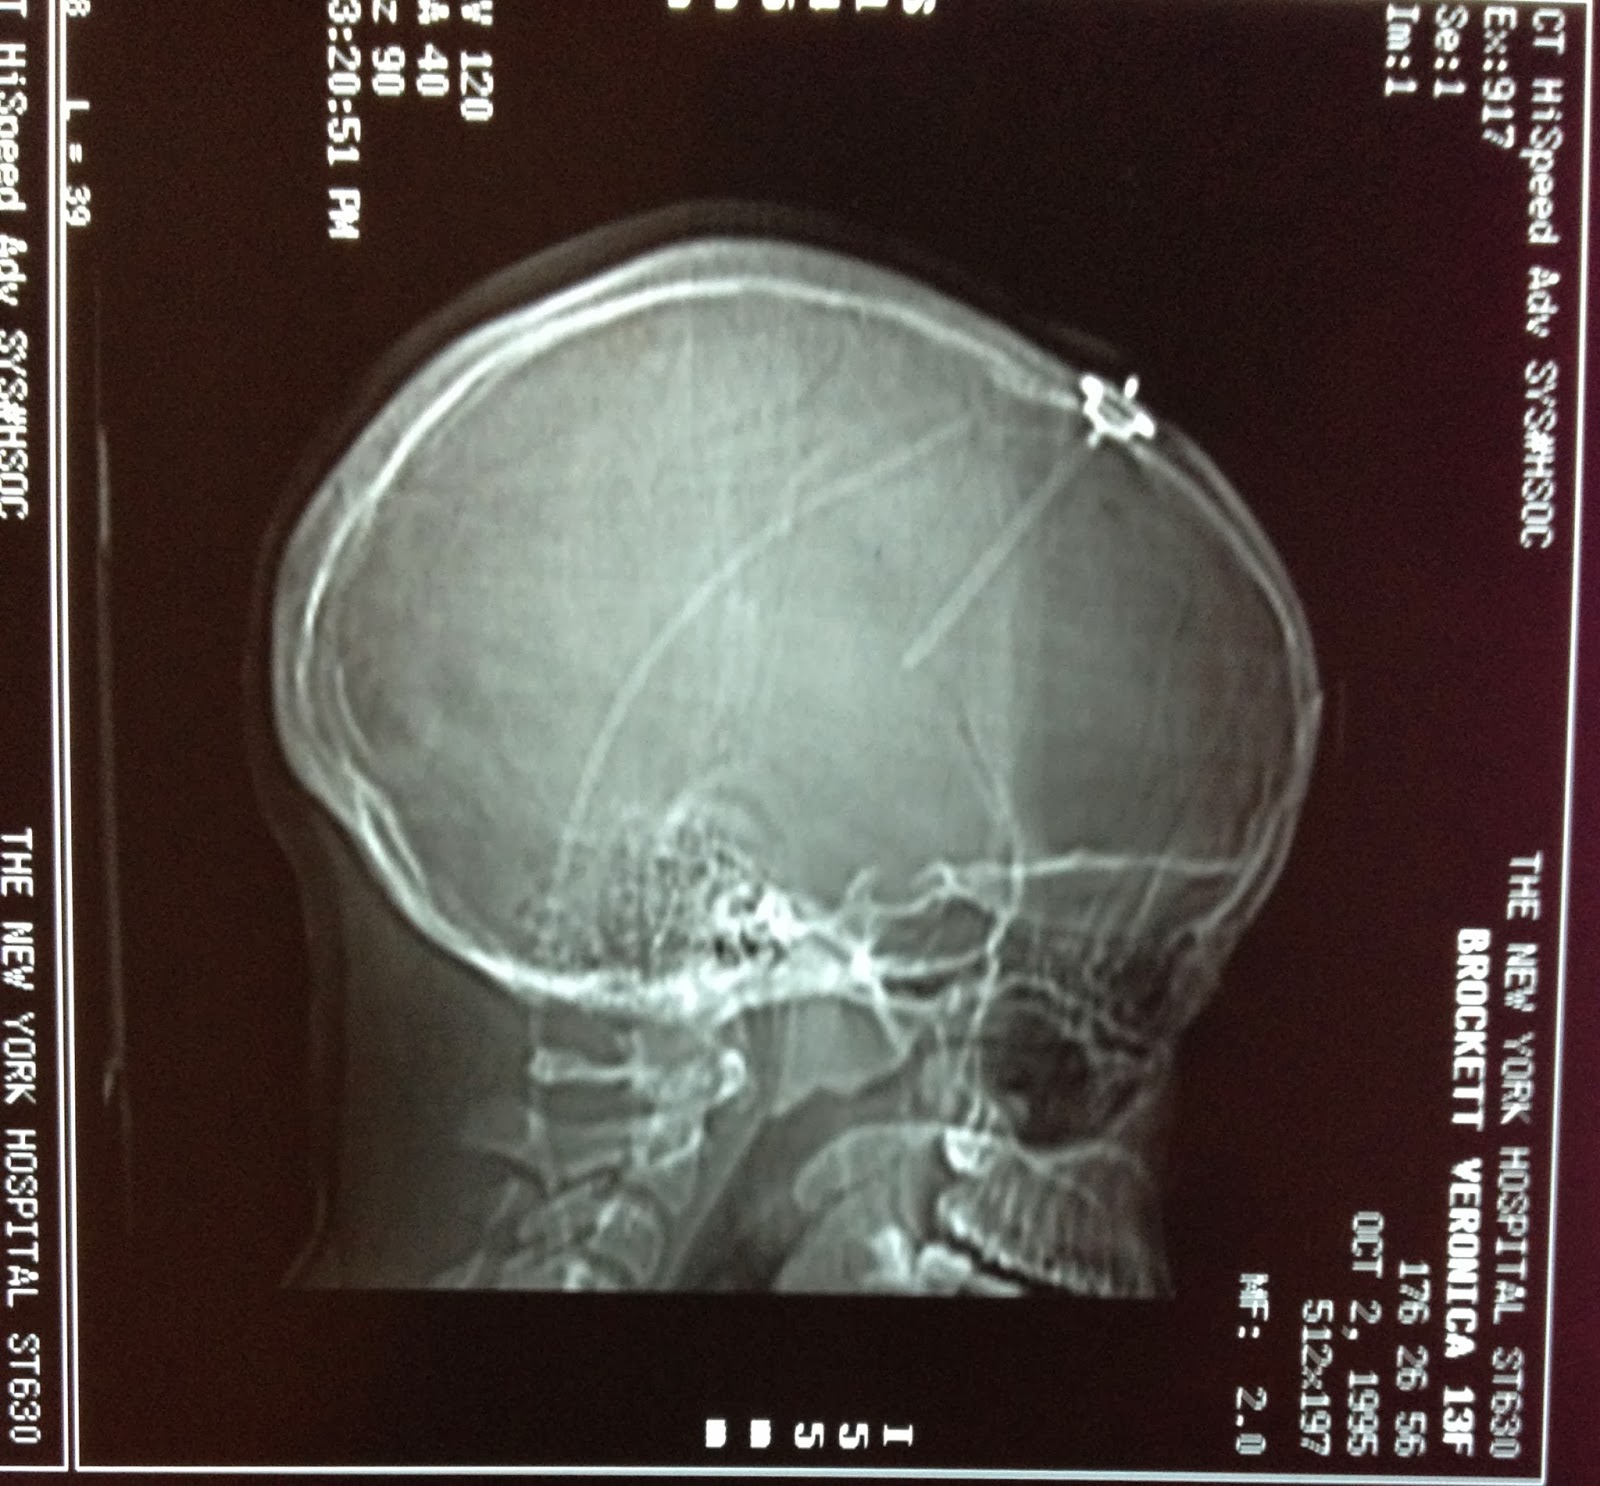

Correct placement of shunt birth to 2009

On March 6 I had my anticipated shunt revision surgery.  In 2009, my shunt had been placed on the wrong side of my brain by a different doctor.  During the surgery (2014) my shunt stopped working because it had been on the wrong side for 5 years. The ventricular catheter was leaking csf fluid all over my brain. While the surgeon was replacing my shunt valve, I had a 10 millimeter intracranial brain hemorrhage on the left side of my brain. The bleed led to a hemorrhagic stroke by my brain stem which was followed by a traumatic brain injury.

When the catheter was returned to the right side of my brain, I had a 5 millimeter intraparenchymal

brain hemorrhage.